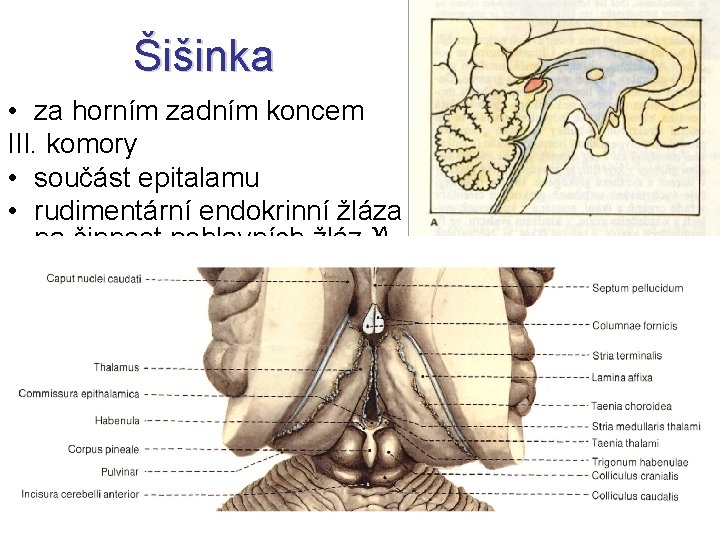

Šišinka Glandula pinealis; Corpus pineale „Epiphysis; Nadvěsek mozkový“ • vývojový vztah k parietálnímu oku • hatérie novozélandská (Sphenodon punctatus) • reakce na polarizované světlo (měsíční biorytmy)

Šišinka • za horním zadním koncem III. komory • součást epitalamu • rudimentární endokrinní žláza s tlumivým účinkem na činnost pohlavních žláz pubertas praecox • dorzálně vybíhá nad mozkový kmen (nad čtverohrbolí středního mozku) • melatonin změna hladiny během dne • acervulus cerebri (= vápenaté konkrementy u dospělých) – CT, MRI